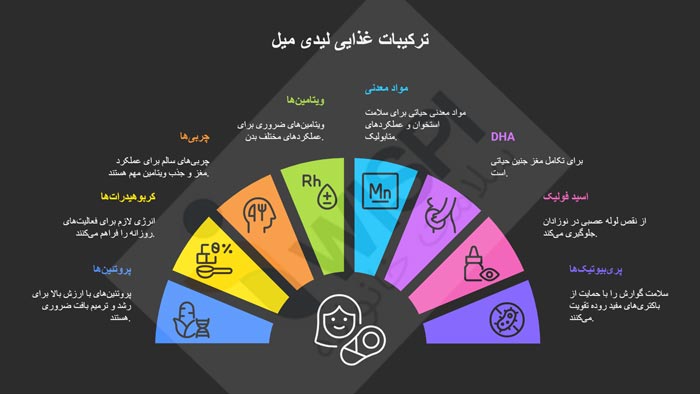

ترکیبات کلیدی لیدی میل و نقش آنها در تغذیه

ترکیبات لیدی میل شامل پروتئینهای با ارزش بالا، کربوهیدراتها، چربیهای سالم، ویتامینها (مانند A، B، C، D، E، K) و مواد معدنی (آهن، کلسیم، روی، منیزیم) است. همچنین حاوی DHA برای تکامل مغز جنین، اسید فولیک برای جلوگیری از نقص لوله عصبی، و پریبیوتیکهایی مانند اینولین برای سلامت گوارش است.